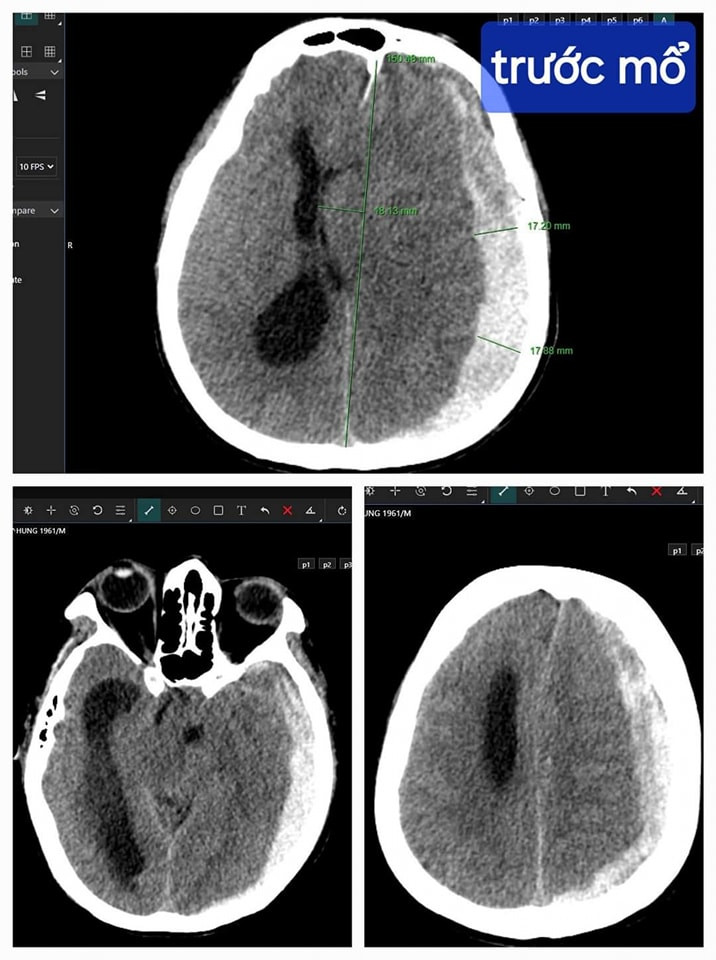

![]() |

| Hình ảnh tổn thương não của bệnh nhân trên phim chụp - Ảnh BVCC |